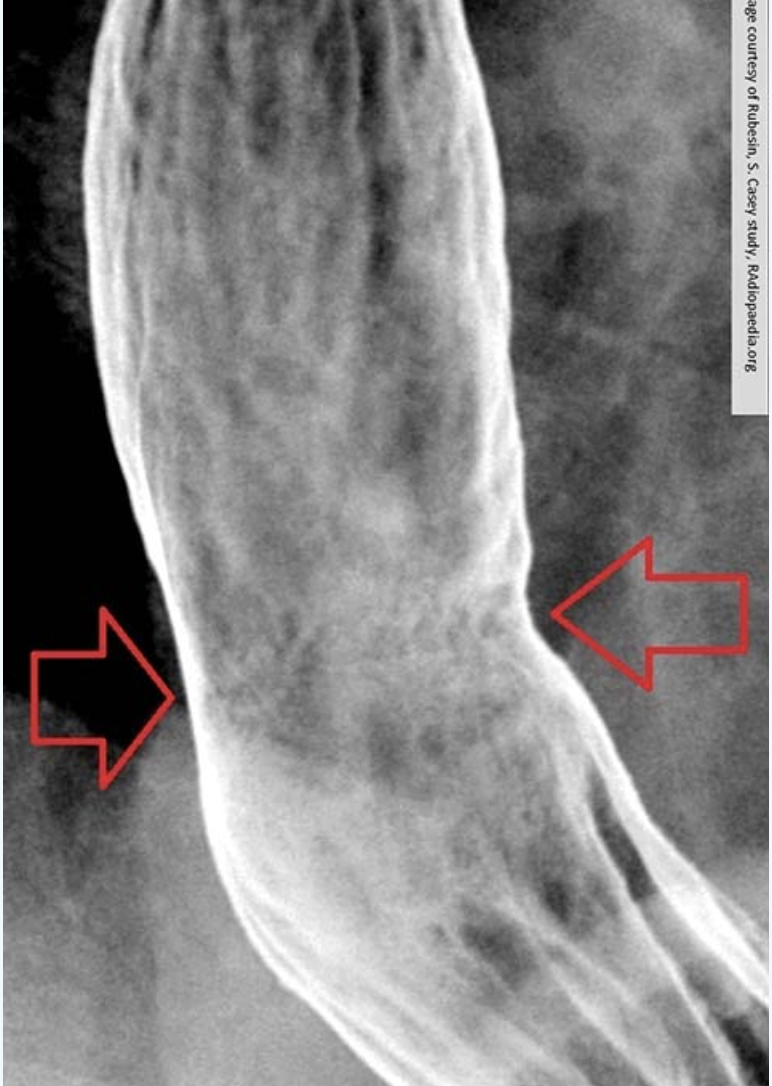

RA of GERD

Barium Swallow with UGI procedure is the standard for assessing GERD

*As GERD progresses, its appearance changes on imaging*

this image is early stage

advanced stage of GERD

Obvious narrowing of the lower esophagus due to reflux. Notice the erosion.